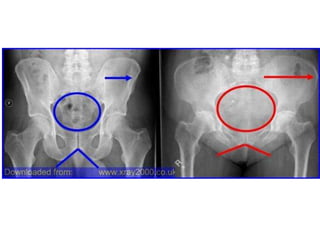

Note the oblique minimally

displaced distal radial

fracture, which extends to

the growth plate and then

laterally along the plate.

Salter Harris Type I Fracture (along growth plate)

Note the obliqueminimally displaced distal radial fracture, which extends to the growth plate and then laterally along the plate.

Salter Harris TypeI Fracture (along growth plate)